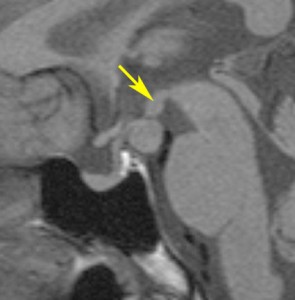

少年期にgelastic seizureで発症

少年期に難治性の発作を生じて悪化しました,これを有茎 pedunculated とするかどうか微妙なところです